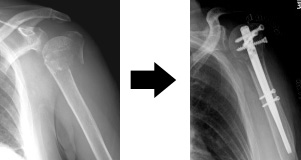

上腕骨近位端骨折について こんな時は救急外来へ 症例別q A 社会医療法人 有隣会 東大阪病院 大阪市 城東区

上腕骨近位端骨折 一般社団法人 日本骨折治療学会 骨折の解説

上腕骨近位端骨折その2 愛知県岡崎市 整形外科 リウマチ科 エコーガイド下筋膜リリース ませぎ整形外科

骨折日記 今回の手術内容 新しいことを知るのって楽しい

骨科部 骨折治療健保鋼板與互鎖式鋼板的選擇 中山醫學大學附設醫院